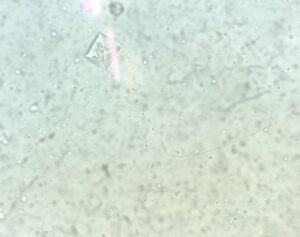

尿中ストラバイト結晶